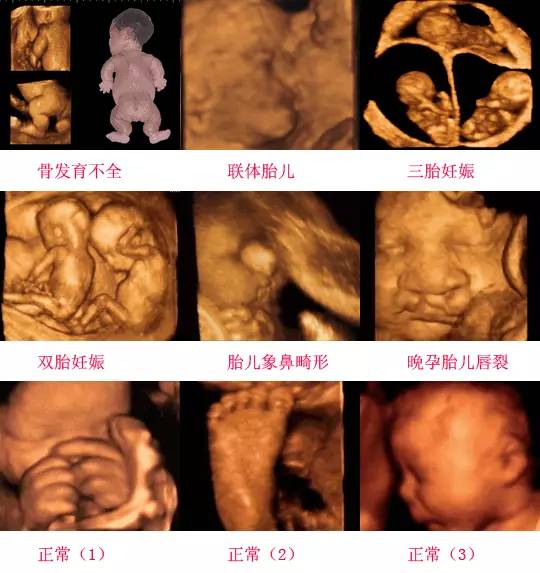

四維彩超是一種先進的醫(yī)學(xué)影像技術(shù),通過實時觀察胎兒在母體內(nèi)的活動情況,為醫(yī)生提供了豐富的診斷信息,在四維彩超下,我們可以清晰地觀察到胎兒的蛋蛋(睪丸)的形態(tài)、位置和大小等特征,胎兒蛋蛋是男性生殖系統(tǒng)的重要組成部分,對于胎兒的生長發(fā)育具有重要意義。

在四維彩超下,胎兒蛋蛋呈現(xiàn)出特定的形態(tài)和外觀,通常情況下,胎兒蛋蛋呈現(xiàn)出圓形或橢圓形,表面光滑,內(nèi)部回聲均勻,隨著胎兒的發(fā)育,蛋蛋會逐漸增大,并呈現(xiàn)出明顯的性別特征,醫(yī)生可以通過四維彩超技術(shù),對胎兒蛋蛋的大小、形態(tài)和位置進行評估,以判斷胎兒生殖系統(tǒng)的健康狀況。

胎兒蛋蛋的發(fā)育是一個復(fù)雜的過程,受到多種因素的影響,在胎兒發(fā)育的早期階段,蛋蛋位于腹腔內(nèi),隨著胎兒的生長發(fā)育,蛋蛋逐漸下降至陰囊,這個過程受到激素、遺傳和環(huán)境等多種因素的影響,在四維彩超的觀測下,我們可以實時了解胎兒蛋蛋的發(fā)育過程,及時發(fā)現(xiàn)異常情況并采取相應(yīng)的治療措施。

四維彩超技術(shù)在評估胎兒蛋蛋發(fā)育方面具有重要意義,通過四維彩超,醫(yī)生可以實時觀察胎兒蛋蛋的形態(tài)、位置和大小等特征,了解胎兒生殖系統(tǒng)的發(fā)育情況,四維彩超還可以幫助醫(yī)生發(fā)現(xiàn)可能的異常情況,如睪丸未降、睪丸囊腫等,為及時采取治療措施提供依據(jù)。